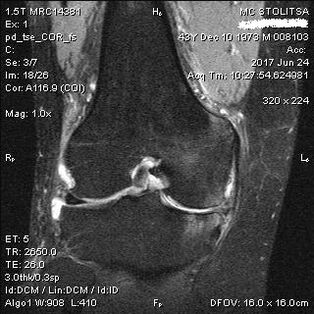

Cancanta na Arthrosis na gwiwa a gwiwa yana faruwa a cikin ofishin wani rhumator masanin ilimin likitanci ko Orthopedist. Likita ya yi nazarin hadin gwiwar da ya shafa, ya mamaye shi, yana sauraron gunaguni da kuma nemi ƙarin tambayoyi. Yayi gwaje-gwaje da yawa - alal misali, suna tambayar mai haƙuri ya tanƙwara kafa ko tafiya kaɗan. Bayan haka, idan ya zama dole a fayyace mataki na cutar ko yanayin canje-canje na ilimin harshe, zai nuna muku ƙarin bincike. Misali, don subography ko radiography.